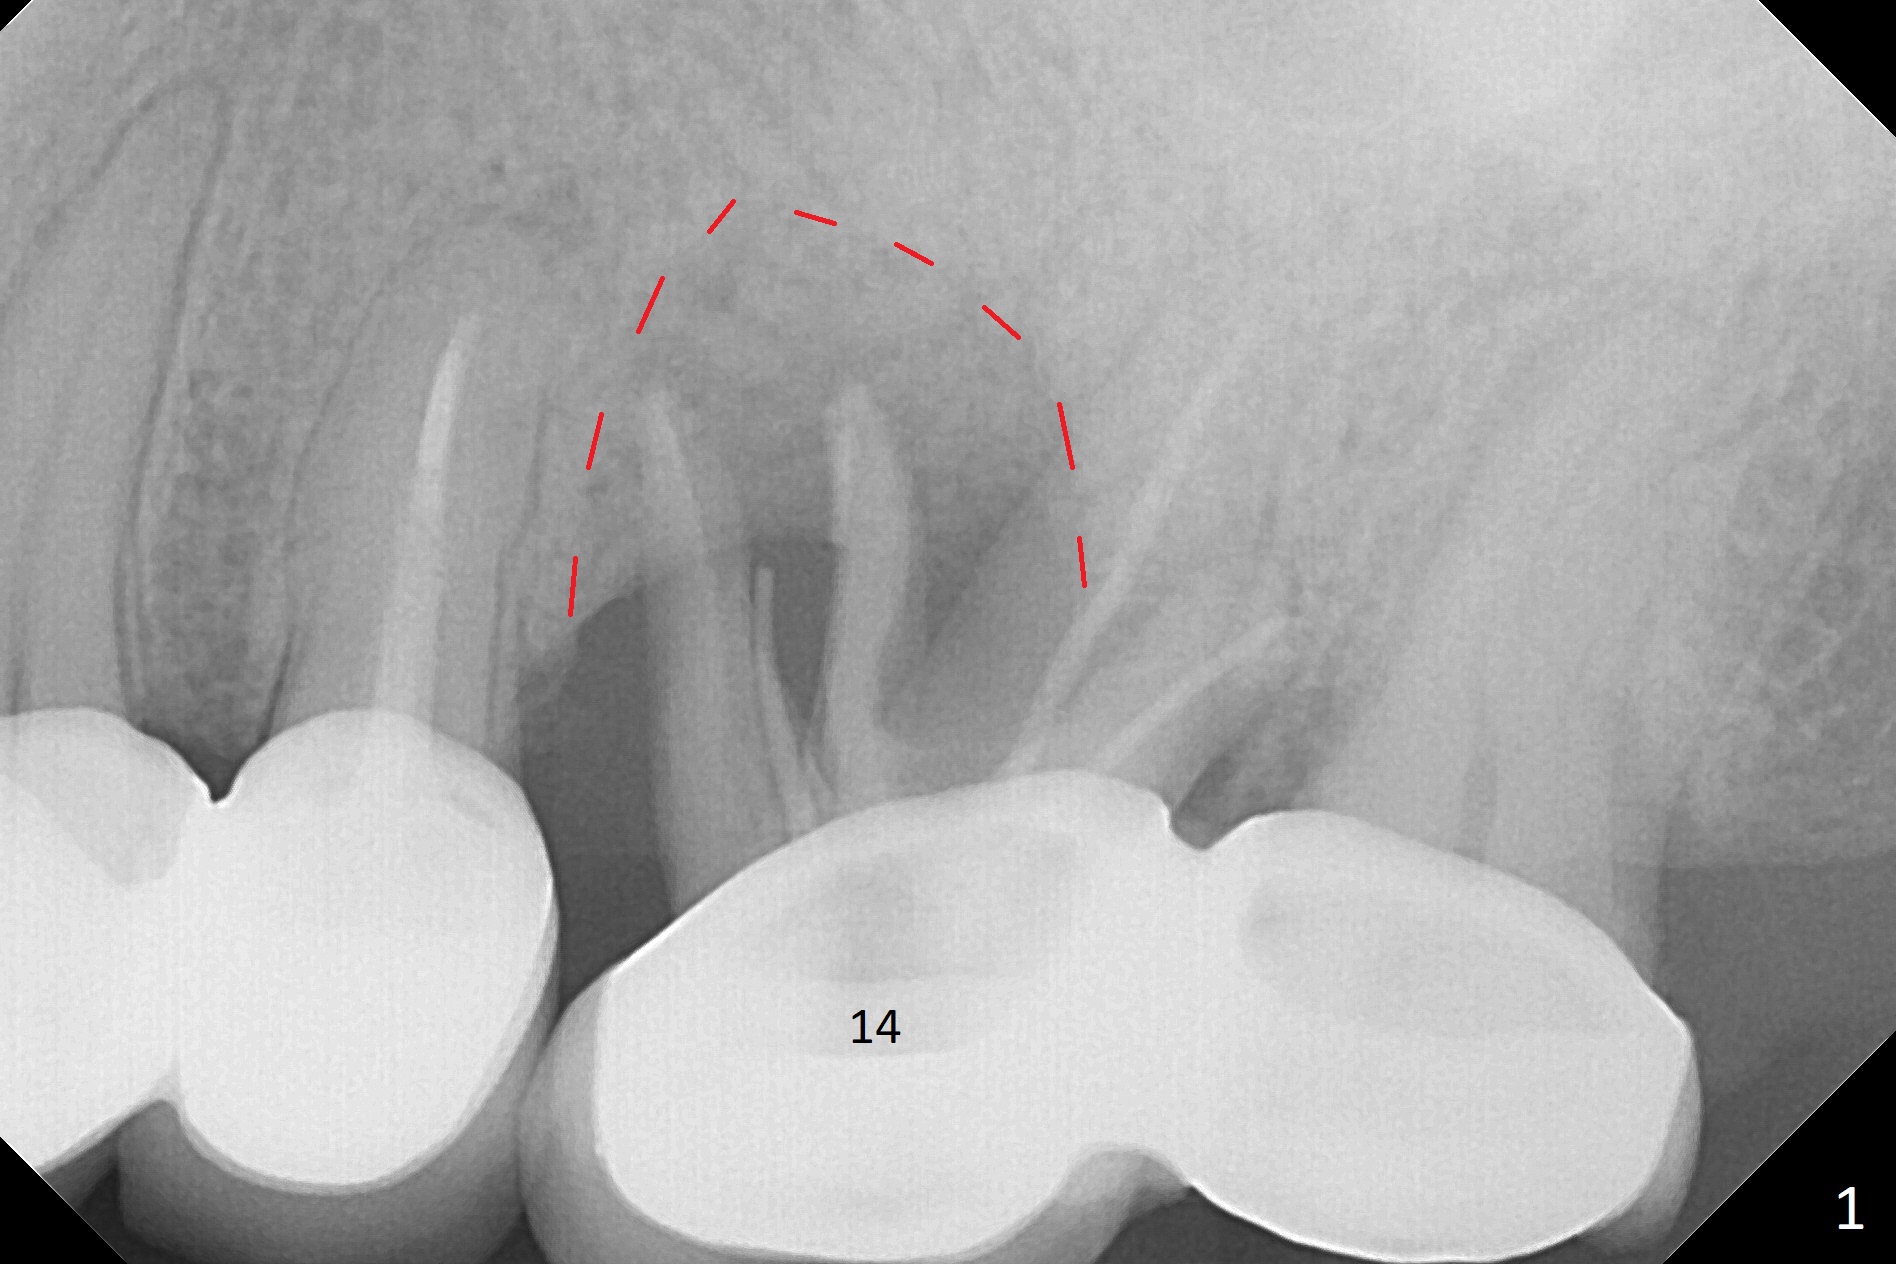

A 49-year-old woman returns for removal of the tooth #14 with loss of the buccal plate (Fig.1 red dashed line). After extraction, the buccal gingiva collapses as a dimple (Fig.2 ^). Cytoplast, a Titanium-Reinforced Non-resorbable Membrane (Fig.3), is used after bending (Fig.4) to assist in repair of the buccal plate with bone graft (Fig.5,6). As compared to Fig.1, the bone height also increases. Periodontal dressing and Cytoplast dislodge with odor 10 days postop (Fig.7,8). Periodontal dressing is re-applied. Spacer or acrylic dressing should have been used for security. In spite of the narrow ridge 5 months postop (Fig.9), a 5x11.5 mm bone level or 5x17 mm tissue-level implant is possible (Fig.10). But the implant should be placed more palatal, away from the buccal defect!